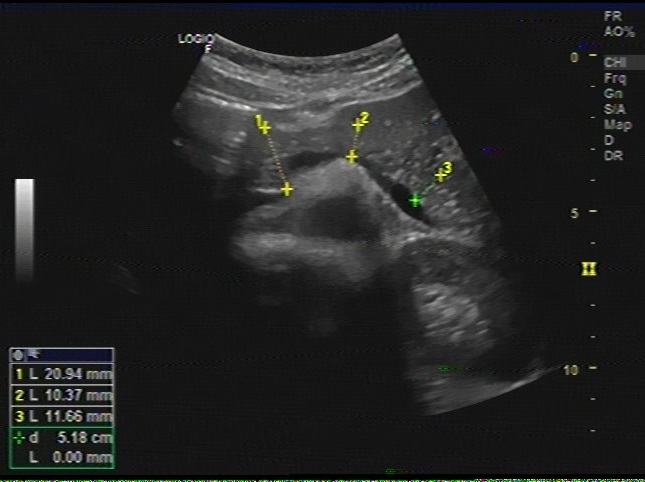

Le pancreas en coupe transverse de

l'abdomen. L.examene se realise a jeune pour diminue

de l'interposition aerique digestives . Et

remplisage de l.estoma par l'eau peut fournie une

fenetre ascoustique pour etudie le corp et le queue

|

Meme cas en coupe oblique

reference . Pancreas est hyper ascoustique

que le foie et se voyait tres nette sur ce coupe |